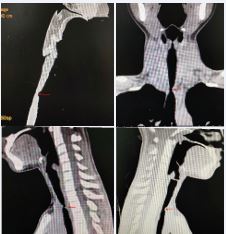

Examination: Physical examination revealed inspiratory dyspnea with mild sternal retractions. Laryngoscopy revealed a 4 mm scar-induced tracheal stricture. Normal vocal cord mobility (Figure 4). Neck CT confirmed a 1.5 cm tracheal stenosis with a 4 mm narrowest diameter (Figure 5).

Figure 5 Preoperative 3D airway CT reconstruction identifies critical stenosis at the cervical trachea (arrow).